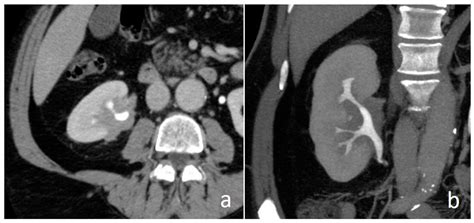

• Ultrasound: An ultrasound of the kidneys and urinary tract is the primary diagnostic tool for detecting pelviectasis. It provides detailed images of the renal pelvis and can help determine the extent of dilation.

• Magnetic Resonance Urography (MRU): This non-invasive imaging technique uses magnetic resonance imaging (MRI) to provide detailed images of the urinary tract. It is particularly useful for evaluating complex cases of pelviectasis.